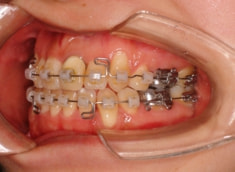

治療開始時

治療法:表の矯正(T21ブラケット)

ご出産のため治療中断期間あり